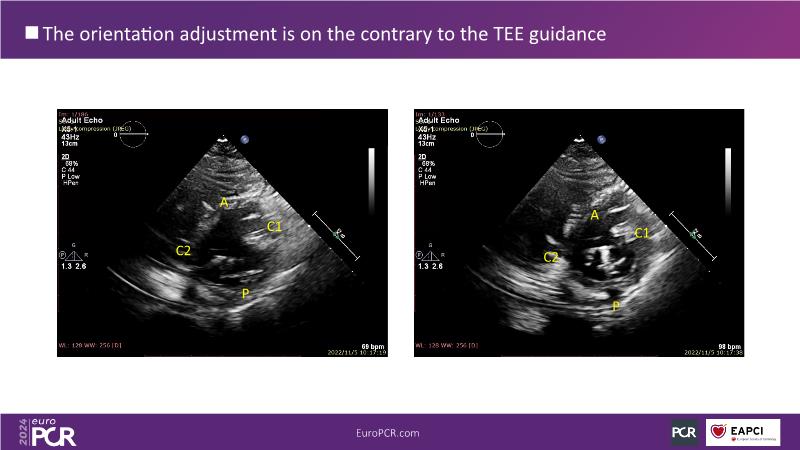

Watch this session to gain insights into the clinical evidence of mitral TEER therapy for the Asian population, learn techniques for implanting a MitraClip in patients with challenging anatomy, and understand how to use the four clip sizes for optimal outcomes. The session also covers educational aspects of clipping in dextrocardia, the benefits of reserve bending of the transseptal needle for tenting and puncture, new steering maneuvers for dextrocardia patients, and the importance of understanding anatomy and collaborating closely with the echo team for success.